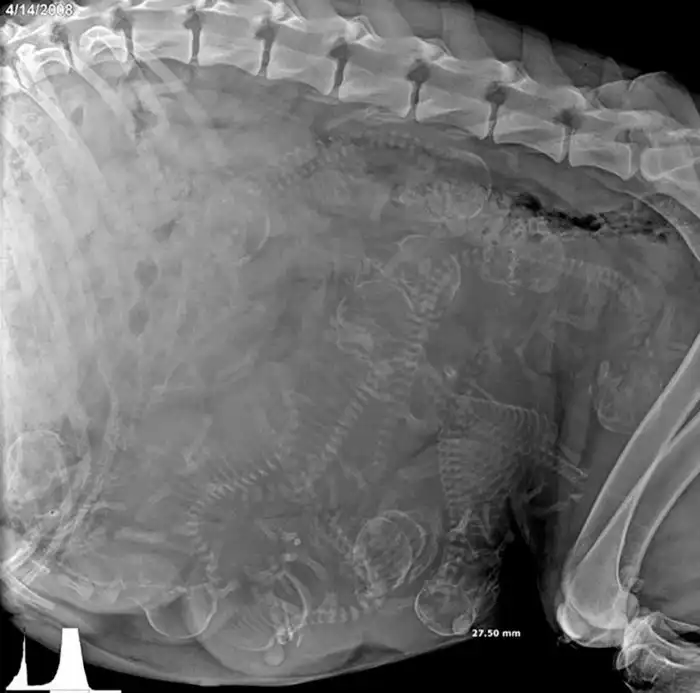

Рентген беременной собаки